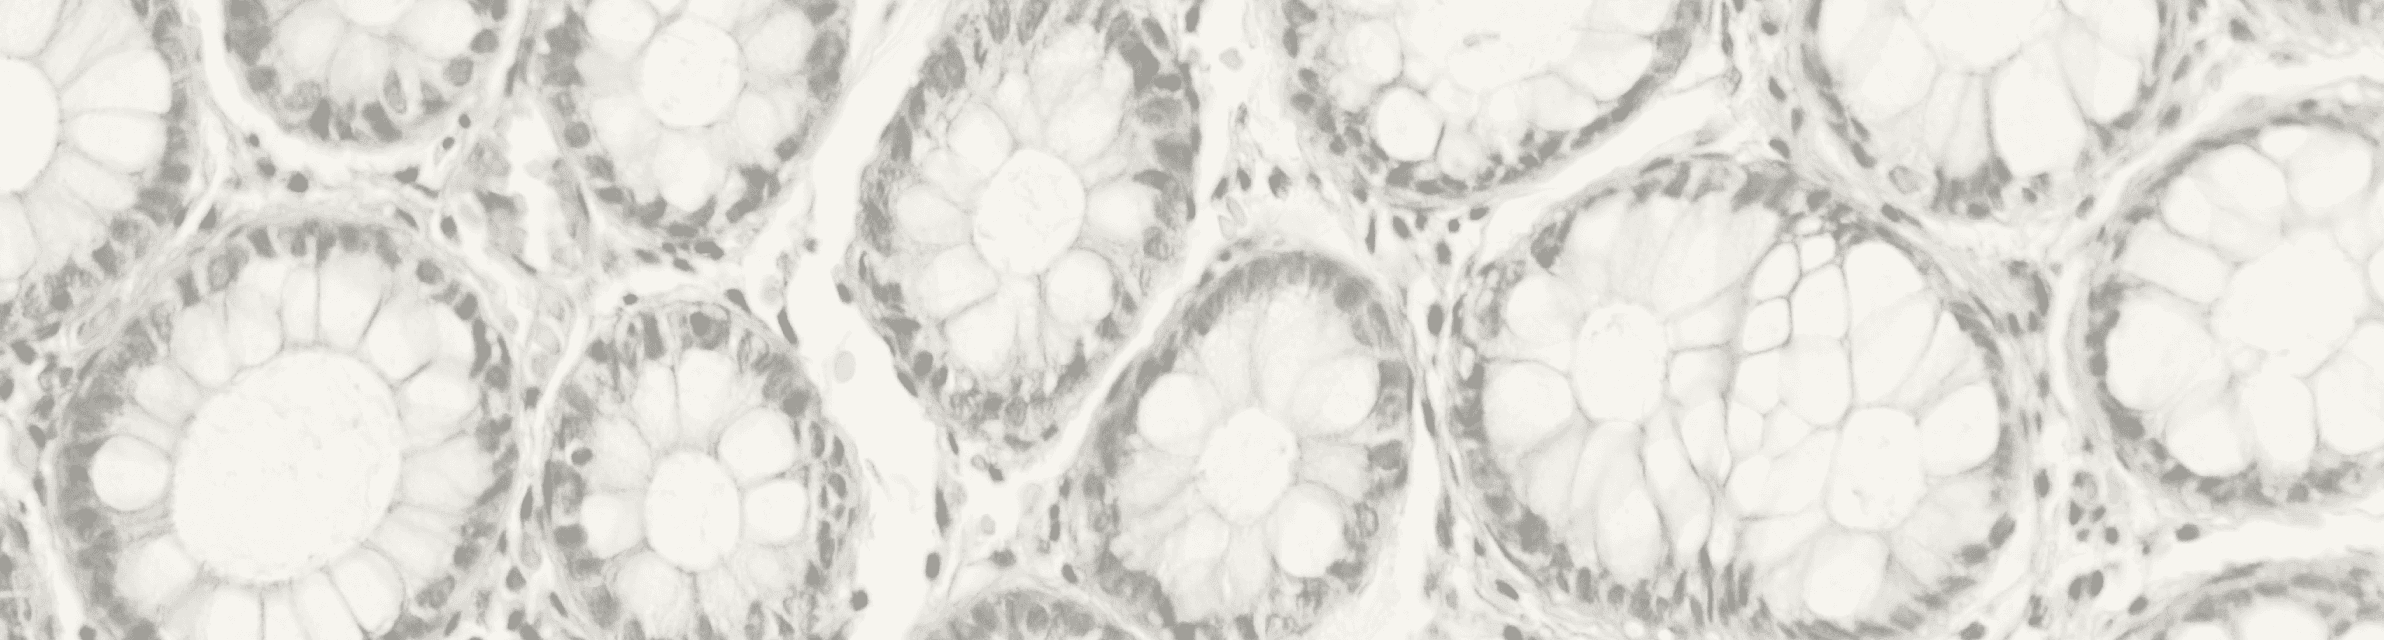

Support for Gastrointestinal Disorders

Clinical research has explored the use of bovine colostrum in managing gastrointestinal conditions. For instance, supplementation has been linked to improvements in symptoms of inflammatory bowel disease (IBD) and other gut-related disorders, highlighting its potential therapeutic role.